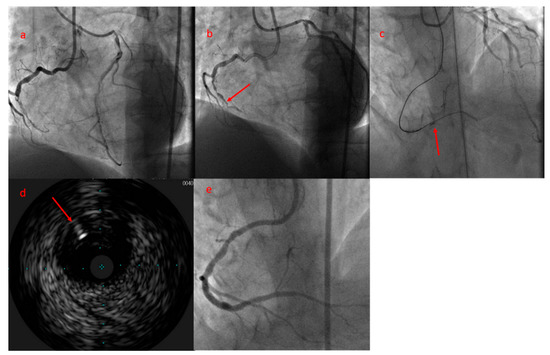

The comparable CTO-PCI success rate between first attempt and reattempt group is in contradiction to the j-CTO stratification, which provides one negative predictive point to reattempted CTOs. This paradoxical situation (“paradox of second attempt”) can have several explanations. Firstly, the first attempted CTO-PCI can serve as an investment procedure as a final resort in order to facilitate the success rate in a new attempt as we explained previously [16]. Secondly, the success rate of a CTO-PCI is highly operator-dependent, and at times seasoned operators can achieve a high success rate, even in highly complex CTOs [17]. The operator’s expertise is a crucial factor along with anatomical variables for a procedural success. Indeed, a new scoring system proposed by our group (E-CTO score) to predict the procedural success comprises the operator’ expertise in a cohort characterized by growing experience in the field of CTO-PCI [18]. Finally, as it has been evidenced in other studies, the operators invest more time and use more complex techniques in reattempted procedures since the meticulous review of previous failed cases can highlight the design of a better strategy and techniques not necessarily used in the first attempt such as retrograde approach, reverse CART, and IVUS guided for antegrade wire re-introduction into true lumen [19,20]. This latter technique consists of positioning the IVUS probe in false lumen, and re-introduction of a second wire into true lumen guided by IVUS was used in two reattempted CTO-PCIs in our series, which revealed again the use of more complex techniques in repeated PCI group (Figure 3).

Figure 3. (a) Bilateral injection shows an RCA-CTO with 47 mm length. During the first attempt, balloon dilatation in CTO body as a bailout technique was used. (b) Coronary angiogram during the second attempt shows CTO body more visible, at least in its first segment (arrowhead), and the CTO length was reduced to 28 mm as a consequence of SPM in the previous procedure. (c) The antegrade wire navigated subintimally, and by positioning the IVUS probe in subintimal space (arrowhead), a new wire penetrated into true lumen. (d) IVUS shows that the true lumen is compressed between 9 and 12 o’clock, and a new dedicated wire is being penetrated into true lumen (arrowhead). (e) Final angiographic result. CTO: chronic total occlusion; RCA: right coronary artery; SPM: subintimal plaque modification.